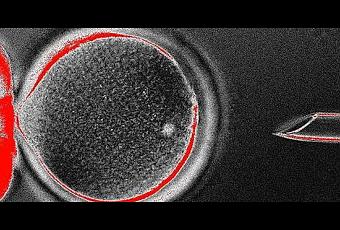

La investigación promete reavivar el debate bioético sobre los experimentos con embriones. Y es que científicos de la Oregon Health & Science University y del Centro de Investigación Nacional de Primates de Oregon (ONPRC) han obtenido células madre a partir de embriones humanos clonados con fines terapéuticos. El hallazgo, basado en un método similar al que se usó para crear la famosa oveja Dolly, podría permitir restaurar el daño causado por un lesión o una enfermedad.

El método de Mitalipov tiene varias ventajas sobre el uso de células madre embrionarias estándar, que se crean a partir de huevos fertilizados: Debido a que las células contienen material genético de un paciente, el cuerpo es poco probable que rechazar las células después de la implantación. El método también utiliza solamente un óvulo donante en lugar de un embrión donante, que algunos defensores antiabortistas pueden estar más dispuestos a tolerar éticamente.